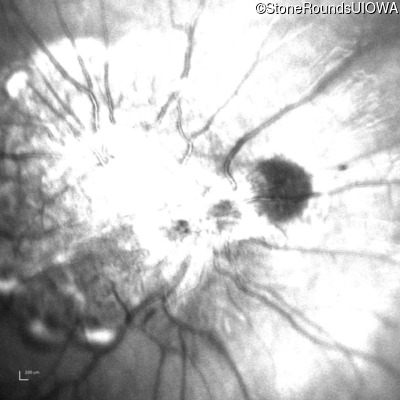

Visit at age: 5 years

Fundus Photography - Right - 20/2000

Exemplar